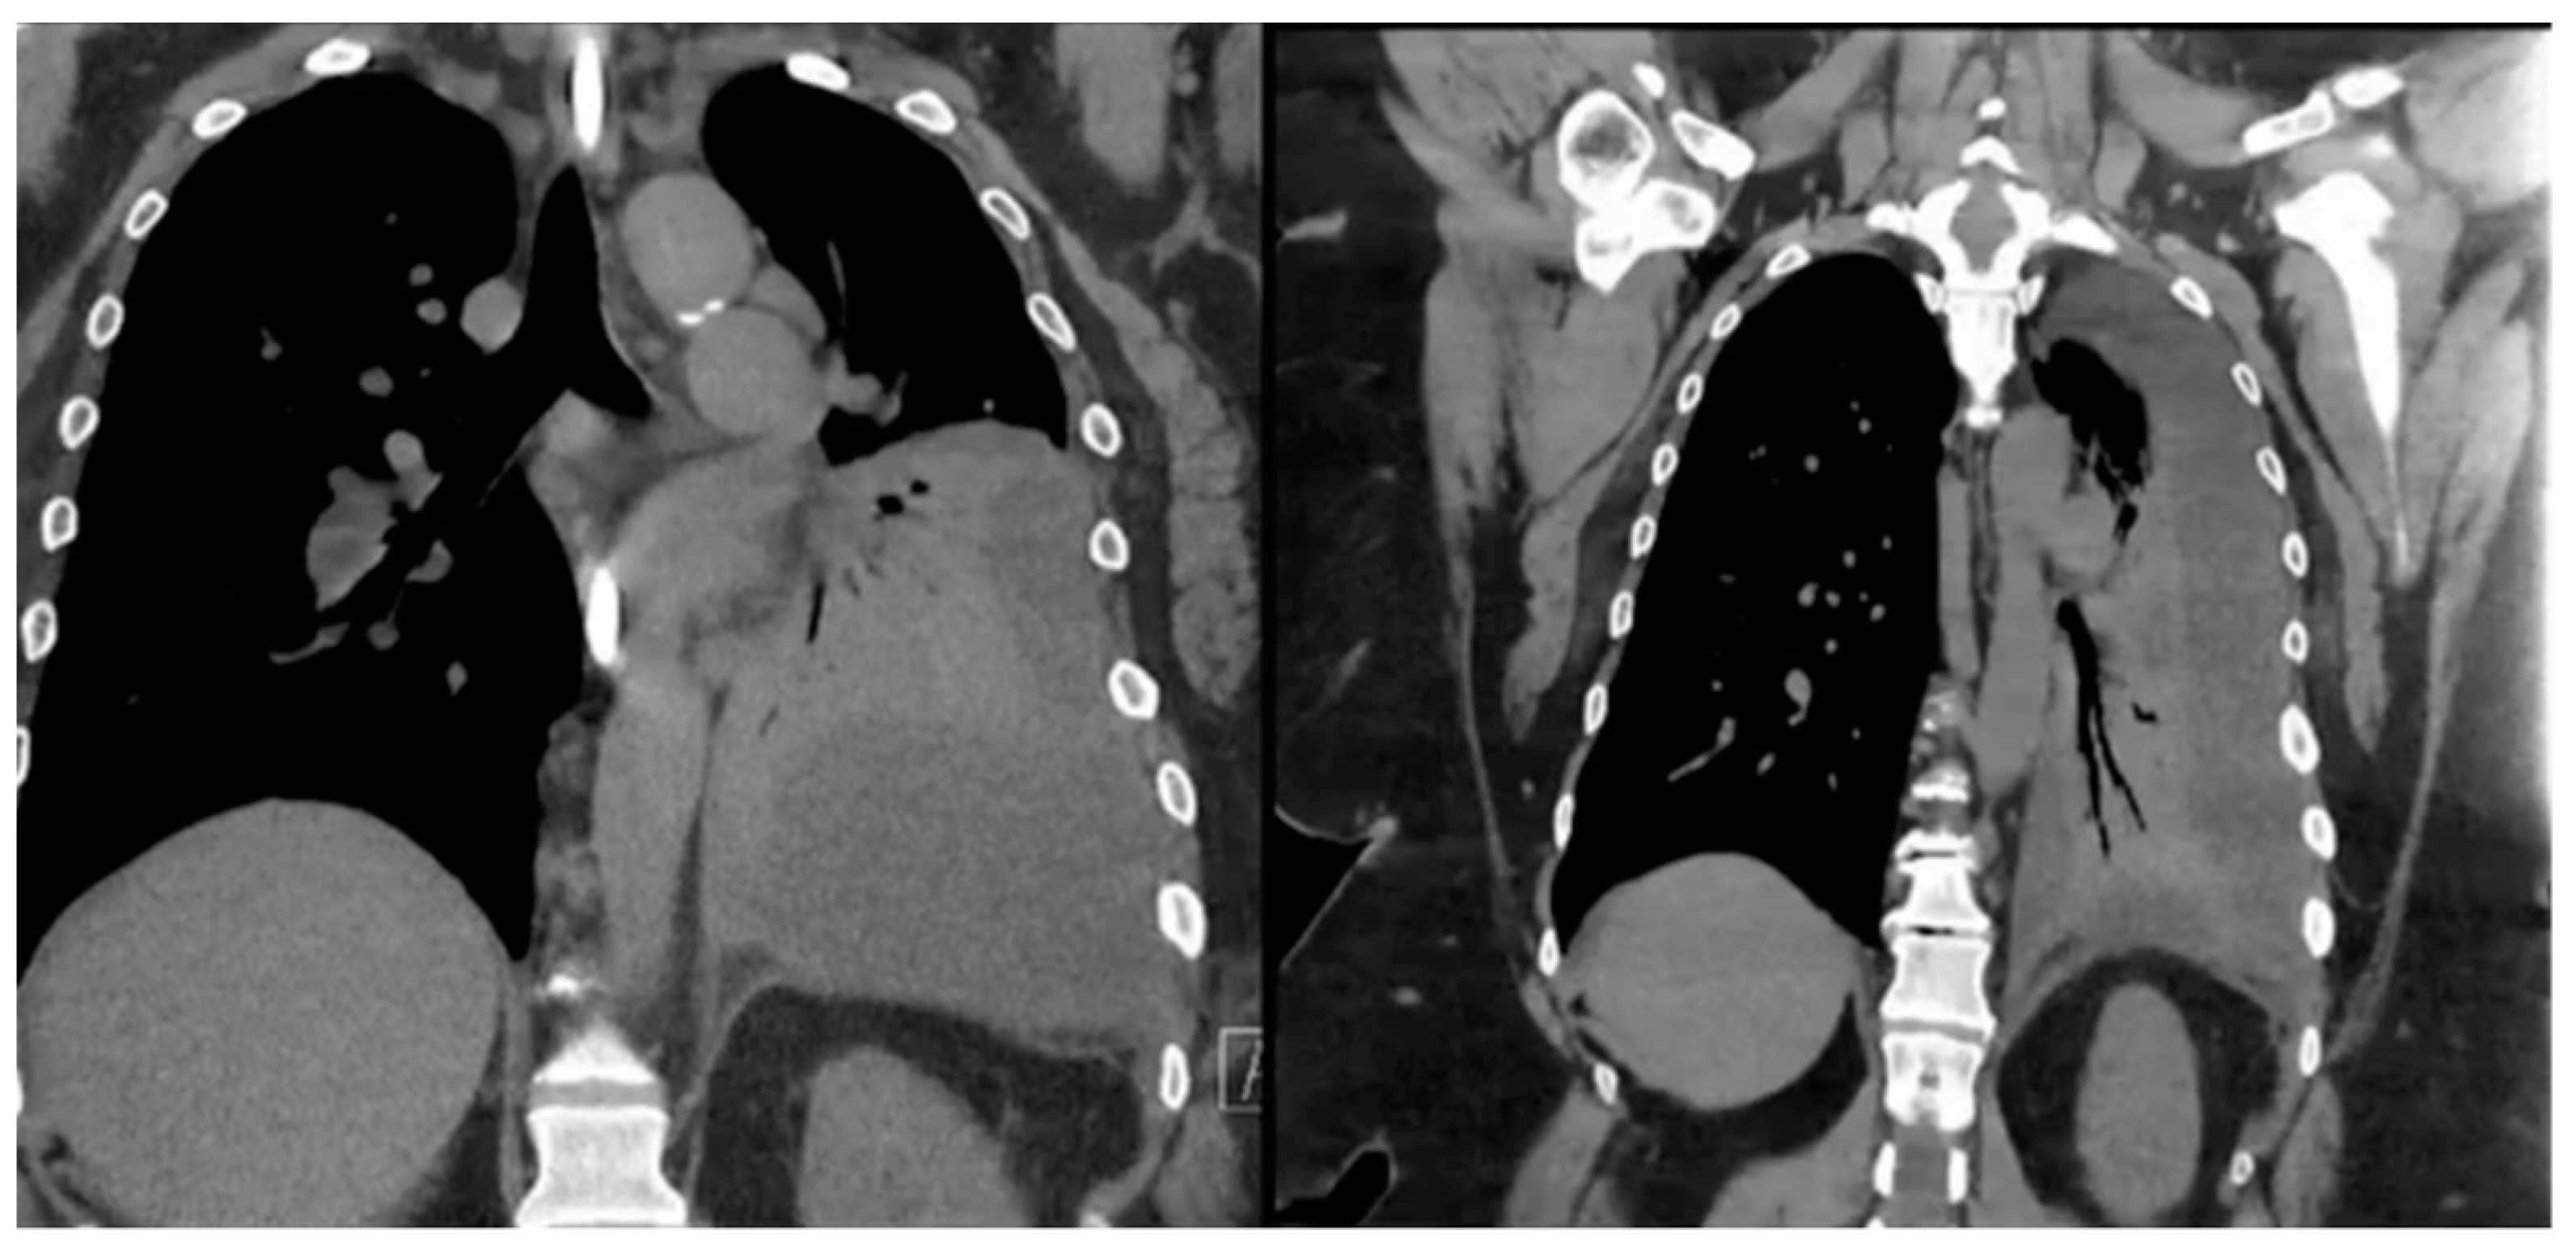

Definitive diagnosis of GBF or GPF is usually made with imaging methods. Diagnostic workup includes a wide variety of imaging modalities showing an aero-digestive communication, such as contrast-enhanced CT, barium swallow, Gastrografin study, or an upper GI series. In some cases, methylene blue swallow can be also used in order to assess the presence of blue dye in the chest tube or percutaneous drainage, aiding in the diagnosis of fistulization (Figure 3). Despite the scarcity of data (due to the rarity of this complication) on the gold standard diagnostic tool, a contrast study of the upper gastrointestinal tract is the widely accepted means of diagnosing these two rare complications after SG [80]. Upper endoscopy itself cannot diagnose GBF or GPF, but it can help identify the fistula origin, define the anatomy, and minimize the need for an invasive approach. However, if coupled with fluoroscopy, EGD becomes the method of choice for diagnosis. Bronchoscopy might be helpful but does not always manage to identify the bronchial fistula orifice even after oral methylene blue administration [79,80,81].

Figure 3.

Chest computed tomography (CT) scan showing obliteration of the left lung space in a patient with gastro-pleural (GP) fistula.